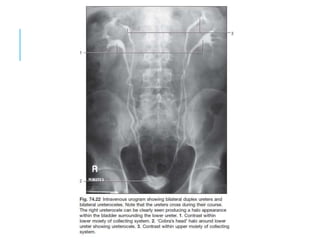

KIDNEY AND URETERS

MODALITY OF CHOICE